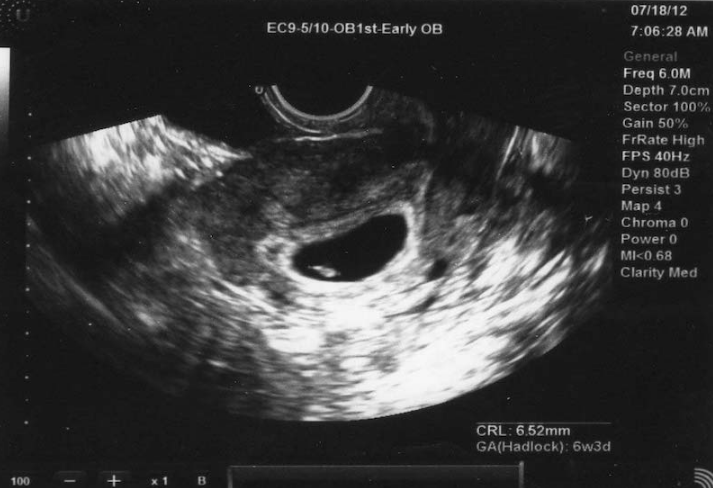

Thông thường, bác sĩ sẽ chỉ định thai phụ thực hiện siêu âm vào tuần thứ 4 đến tuần thứ 6 của thai kỳ. Vì là lần siêu âm đầu tiên nên đây là cột mốc quan trọng với mẹ bầu. Lúc này, siêu âm cũng giúp kiểm tra tim thai, tình hình phát triển của thai và đặc biệt là xem thai đã vào tử cung chưa.

Vậy khi thai 4 tuần siêu âm có thấy không? Khi mẹ bầu siêu âm vào thời điểm này chưa chắc sẽ thấy được em bé vì thai nhi 4 tuần tuổi vẫn còn rất nhỏ, thậm chí còn chưa thể phát hiện tim thai. Đây là quy trình phát triển tự nhiên bình thường của bé. Do đó, thai phụ cần tiếp tục siêu âm vào các tuần tiếp theo của thai kỳ mới có thể thấy em bé rõ hơn. Tuy nhiên, siêu âm vào tuần thứ 4 vẫn cần thiết vì mang lại một số lợi ích.

Ngoài việc băn khoăn xem thai 4 tuần siêu âm có thấy không, các mẹ bầu cũng cân nhắc xem có cần thiết đi siêu âm quá sớm không. Câu trả lời đúng là vào thời điểm tuần thứ 4 - 6 của thai kỳ, các mẹ bầu đều cần thực hiện siêu âm. Qua hình ảnh siêu âm thai nhi 4 tuần tuổi, bác sĩ và mẹ kiểm tra được một số thông tin sức khỏe cơ bản của thai nhi như sau:

Tuy nhiên, như đã nói ở trên, với những bà mẹ muốn biết thai 4 tuần siêu âm có thấy không thì câu trả lời là chưa thể thấy rõ bé vào giai đoạn này.